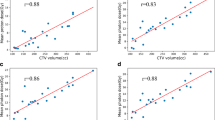

Regarding scalp dose, improved sparing was seen for low, intermediate, and high doses (V5, V10, V20, and V30) with the four- and 13-beam IMRT plans. The seven-beam IMRT plan improved intermediate and high doses (V10, V20, and V30) while only high doses (V20 and V30) were reduced in VMAT plans (Table 4). Compared with the OL technique, the four-field IMRT plan reduced the mean dose to the scalp the most (20.8 % reduction) followed by the 13-field (−19.8 %), seven-field (−13.8 %), and VMAT (−4.8 %). Depending on the DVH parameter, IMRT/VMAT reduced scalp dose by 10–70 %, external ear/auditory canal dose by 2–96 %, and parotid gland dose by 3–31 % (Fig. 2).

On final analysis, of all the treatment planning techniques and potential beam arrangements, the 13-beam IMRT plan achieved the largest dose reduction for the scalp (V10 −10 %, V20 −30 %, and V30 −70 %), external ear (V5 −10 %, V10 −32 %, V20 −28 %, and V30 −96 %), and parotid gland (−31 % mean dose) combined.